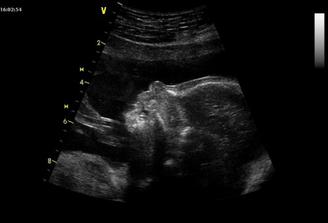

Screening dopadl dobře, máme krásný mímo. Pohlaví jsme si říct nenechali. Váží už 400g. I návštěva u mojí MUDr. dopadla dobře. Další návštěva 18.3. - trochu nám tvrdne bříško a máme menší zánět. 7.4. - přibrala jsem zase pár kilo, dohromady už 9kg. Tvrdnutí bříška neustupuje, i když to tvrdnutí skoro vůbec necítím. Miminko je hodně nízko a prý ho vytlačuju. Budu pracovat z domova a hlavu dolů 🙂 Zánět musíme léčit dál. 21.4. nás čeká screening.